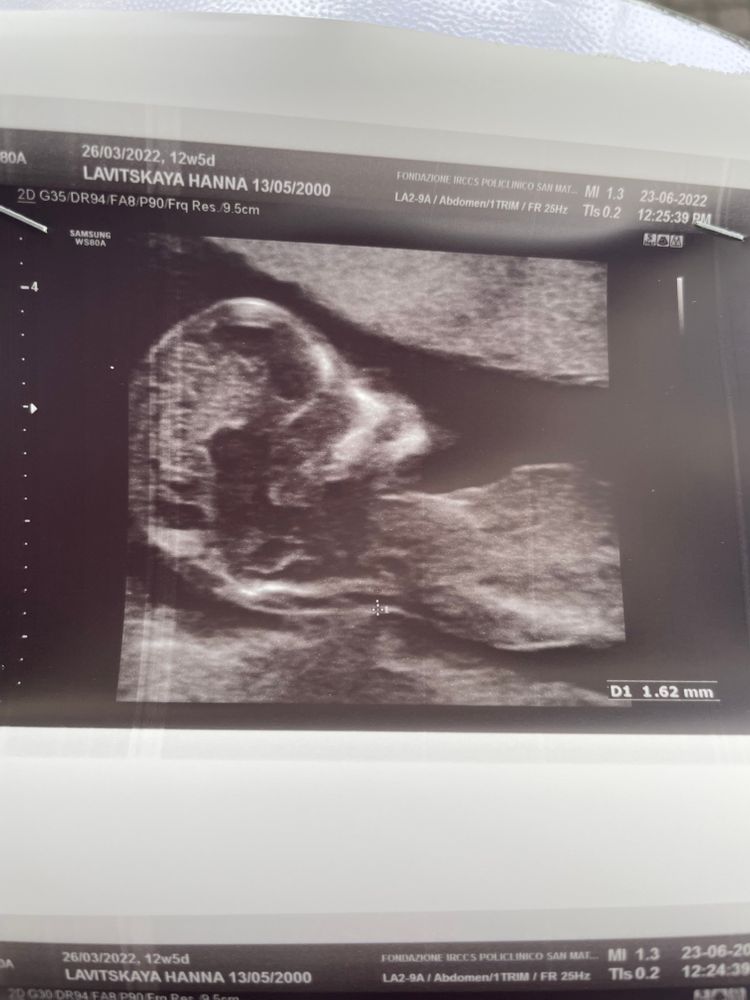

1 скрининг. 12 недель 6 дней

Сегодня прошла первый скрининг. Все отлично, все показатели в норме. За кровь даже не волнуюсь. Наивная я думала, что, возможно, увидят пол, но этот ребятенок стал крутиться как юла. Мне даже сказали выйти походить и съесть что-нибудь сладкое.